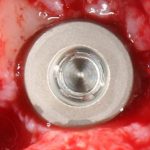

Рекомендации по установке имплантов. Для всех. Часть III